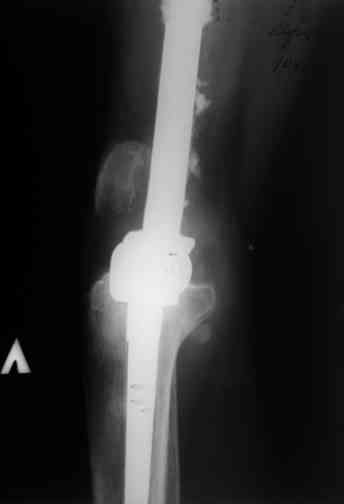

Через 4,5 лет после травмы выявлены рентгенологические признаки консолидации перелома, признаки хронического остеомиелита купировались. Аппарат был демонтирован. Пациент продолжил ходьбу с дозированной нагрузкой на конечность при помощи костылей. Через 2 месяца начал ходить при помощи трости. Однако, еще через 2 месяца отметил появление свищей на бедре с гнойным отделяемым и укорочение длины конечности. При осмотре в январе 2007 г.: пациент ходит при помощи костылей без опоры на левую нижнюю конечность, на бедре имеются множественные рубцы, на наружной поверхности сегмента в верхней и нижней третях имеются два свищевых хода со скудным серозно-гнойным отделяемым; отечности тканей конечности нет, пальпация безболезненная, отмечается укорочение длины конечности на 5 см, патологическая подвижность не определяется, имеется стойкая разгибательная контрактура коленного сустава (разгибание - 180 гр, сгибание - 170 гр), признаков нарушения кровоснабжения и иннервации тканей конечности нет. Температура тела нормальная. В общих анализах крови и мочи отклонений от нормы нет. [image 06,07, 08 (стрелками отмечены свищевые раны, 09, 10]Дорогие коллеги, я уверен, что у многих из вас после знакомства с данным клиническим наблюдением появится множество вопросов, касающихся уже проведенного лечения (особенно, сроков и способов). Сразу оговорюсь - я не смогу правильно ответить на многие вопросы (особенно касающиеся предшествующего периода лечения). Прошу вас, конечно по возможности, сосредоточить внимание не на разборе допущенных ошибок (проведенного лечения), а помочь добрым советом относительно тактики наших дальнейших действий. Наверное, кто-то располагает бесценным опытом лечения подобной патологии.